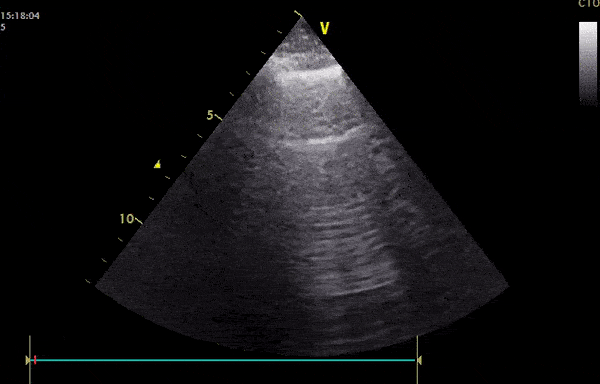

This is an ultrasound clip performed in a 57 year old male patient with known COVID-19 pneumonia. The patient presented with dyspnea and fever, he had an oxygen saturation of 94% on room air. The clip demonstrates an irregular pleural line with numerous B lines present. Interestingly, A-lines are also present that appears to be intermittently erased where B lines cross. Image courtesy of Pierre Bernatas (@pb2316)